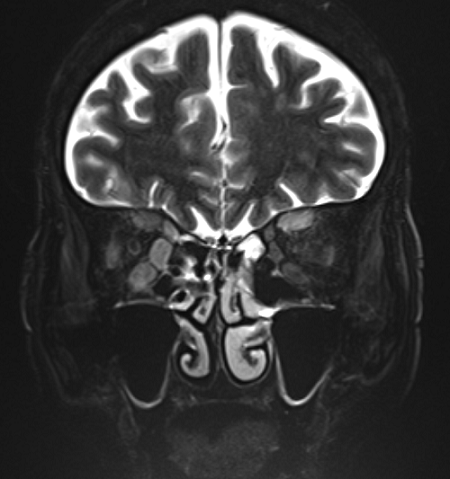

目を動かす筋肉が炎症を起こすと筋肉の動きが悪くなり、患者さんは複視(ものがだぶって見えること)を訴えます。この場合の「だぶり」は、片目で見るとものは一つに見えますが両目で見ると二つに見えることをいいます。検査法としてはコンピュータ断層撮影(CT)や磁気共鳴画像法(MRI)で目の後ろの断層写真を撮って診断します。また、眼窩内の脂肪が炎症を起こしますと、脂肪の体積が増えるため目は押されて出てきます(眼球突出)。出た目は簡単には引っ込みづらく、太った筋肉はもとどおりになりにくくなります。

眼球を動かす外眼筋の筋腹が肥大している。